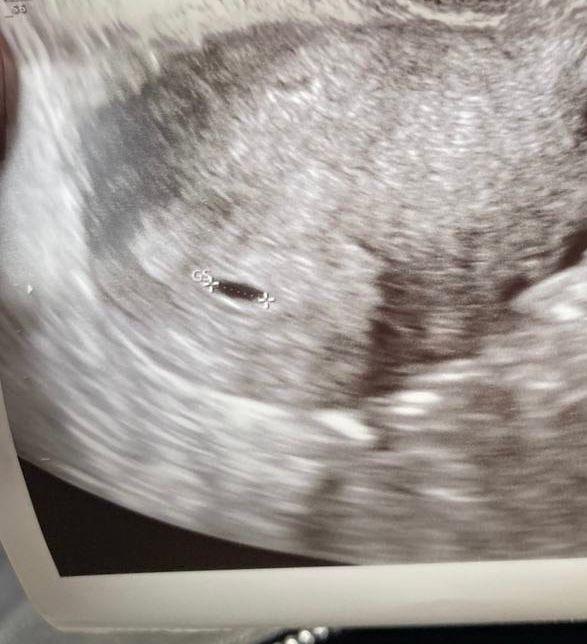

19 дпп первое узи!

Изображение Вот у меня тоже овальное на 15дпп

Ну вот и первое УЗИ! 23 дпп УЗИ